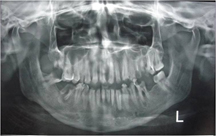

OPG (Orthopantomogram) [Table/Fig-2] of the patient revealed carious #16, 28 and 38, grossly carious 36 and 48, grossly decayed infected #17, 26 and 46 and previously root canal treated # 25 and 27. Root stumps were present #17, #37, 47 were missing.

Pre-operative orthopantomogram